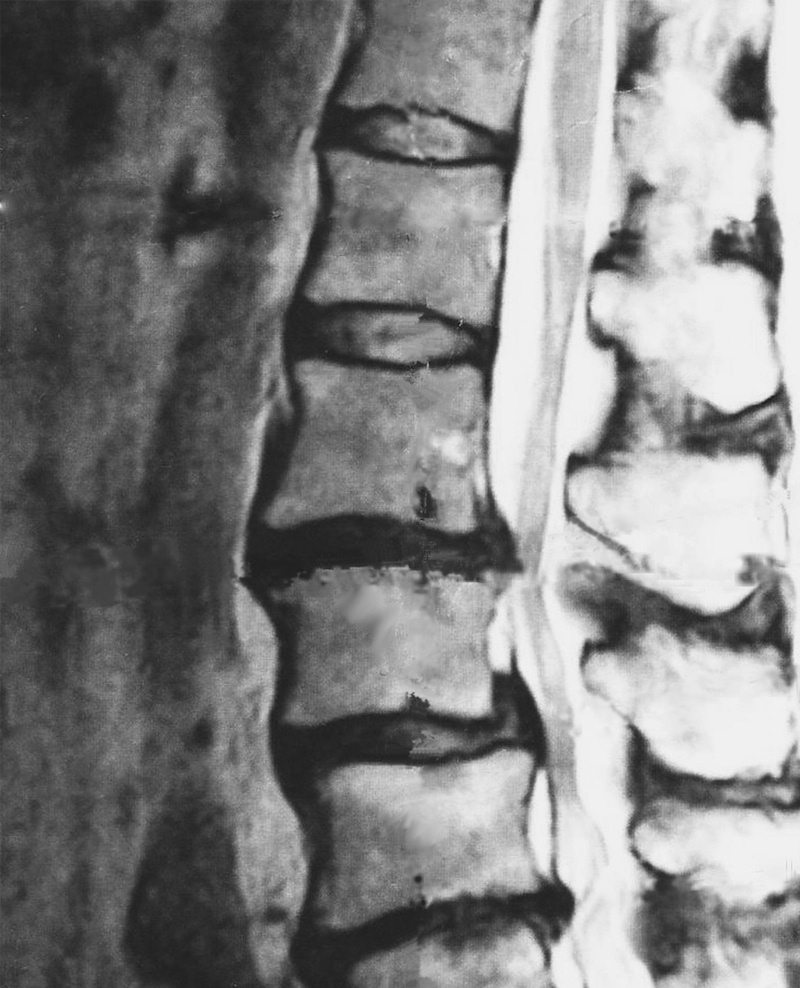

主にMRI検査で腰椎のクッションの役割をしている軟骨である椎間板が飛び出しているという判断のもと診断されます。

飛び出した椎間板が神経を圧迫することにより腰や足の痛み・しびれを発症すると言われています。

しかし、この説明は理にかなっているように感じますが疑問もあります。

腰痛や足のしびれが全く無い方でも椎間板ヘルニアがみつかる場合があります。逆に椎間板ヘルニアがなくても激しい腰痛や足のしびれがある方もおられます。